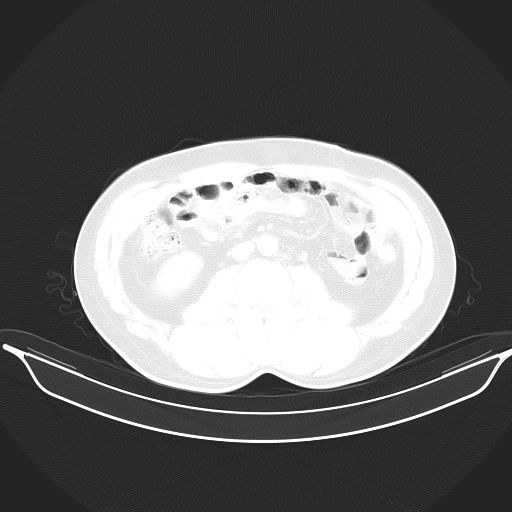

标题: CT25490:男,40岁,体检发现;无其它不适。 [打印本页]

标题: CT25490:男,40岁,体检发现;无其它不适。

考虑右下肺周围性肺癌并肺内多发转移,纵隔淋巴结转移!

支持 !考虑右下肺周围性肺癌并肺内多发转移,纵隔淋巴结转移,(气管前腔静脉后,隆突下,主动脉弓下都有了)

1、均为转移,原发灶不在肺内。2、肺癌肺转移。